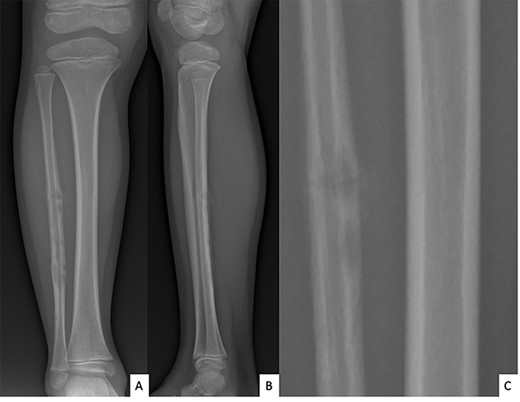

Ultrasound showed a diaphyseal subperiosteal hematoma of the fibula with cortical irregularities. The radiograph showed a pathological fracture, at the upper end of a cortical bone lesion of mixed osteolytic and osteoformative character with bone callus (Fig. 1). MRI showed a multifocal osteolytic cortical process extending along the fibular shaft, without tumor mass in the soft tissues with respect for the signal of the medullary cavity. The perilesional soft tissues were respected, but they appeared in strong hypersignal T2 and enhanced after injection of gadolinium (local inflammatory reaction or post-traumatic changes; Fig. 2).

MRI of the right fibula: coronal MR STIR imaging (A); T1-weighted imaging (B); axial T2 FAT SAT section of the proximal part (C) and distal part (D) of the lesion. MRI shows areas of osteolysis around a medullary cavity narrowed by cortical thickening (sclerosis) and diffuse tissue inflammatory edema leading to suspicion of chronic osteomyelitis.